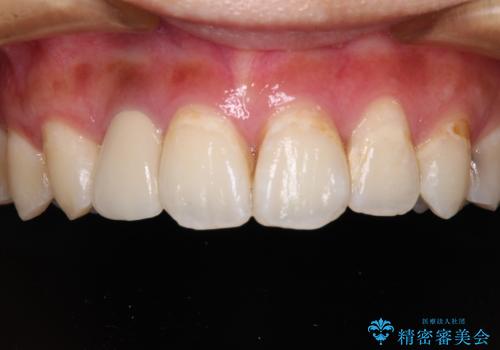

歯が欠けてしまった。オールセラミッククラウンによる補綴治療

- 食事中に歯が欠けてしまった事を主訴に来院された患者様です。

小臼歯が広範囲に欠けてしまっています。

部分的な詰め物では再びかけてしまうリスクが高いため、オールセラミッククランにて補綴治療をすることとしました。